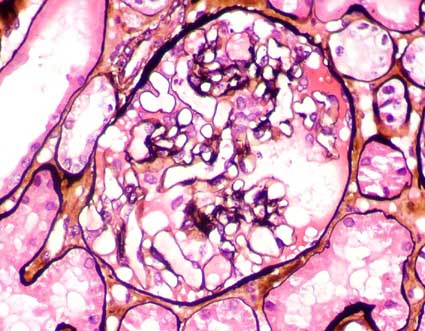

Figure 4.

Methenamine-silver stain, X400.

Figure 5.

Cellularity in mesangial areas near to glomerular hilium is not adequate

to evaluate mesangial hipercellularity (Methenamine-silver stain,

X400).